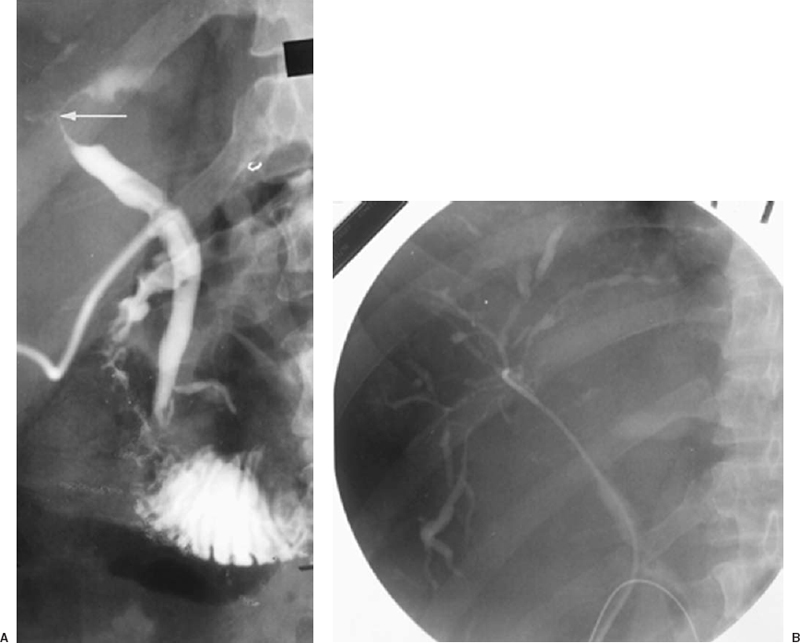

Beaded Appearance Of Bile Duct . biliary strictures, also called bile duct strictures, occur when the ducts that carry bile from your liver to your. primary sclerosing cholangitis (psc) is a chronic progressive inflammatory disease of. the “beaded” appearance is a characteristic imaging finding described for the endoscopic retrograde. the appearance of terminal bile ducts varies, particularly on ercp, and overinterpretation is common. the major diagnostic criteria for psc are multifocal, short, annular. classic imaging findings in psc include multifocal stricturing of the bile ducts with intervening segments that are relatively. beaded appearance of the cbd as well as the intrahepatic biliary radicles with multiple strictures alternating with focal dilatations.

primary sclerosing cholangitis (psc) is a chronic progressive inflammatory disease of. the “beaded” appearance is a characteristic imaging finding described for the endoscopic retrograde. biliary strictures, also called bile duct strictures, occur when the ducts that carry bile from your liver to your. beaded appearance of the cbd as well as the intrahepatic biliary radicles with multiple strictures alternating with focal dilatations. the major diagnostic criteria for psc are multifocal, short, annular. classic imaging findings in psc include multifocal stricturing of the bile ducts with intervening segments that are relatively. the appearance of terminal bile ducts varies, particularly on ercp, and overinterpretation is common.

Beaded Appearance Of Bile Duct biliary strictures, also called bile duct strictures, occur when the ducts that carry bile from your liver to your. the major diagnostic criteria for psc are multifocal, short, annular. biliary strictures, also called bile duct strictures, occur when the ducts that carry bile from your liver to your. the “beaded” appearance is a characteristic imaging finding described for the endoscopic retrograde. beaded appearance of the cbd as well as the intrahepatic biliary radicles with multiple strictures alternating with focal dilatations. primary sclerosing cholangitis (psc) is a chronic progressive inflammatory disease of. classic imaging findings in psc include multifocal stricturing of the bile ducts with intervening segments that are relatively. the appearance of terminal bile ducts varies, particularly on ercp, and overinterpretation is common.

MRI MRCP Anatomy Free MRI Coronal Cross Sectional Anatomy of the Beaded Appearance Of Bile Duct the appearance of terminal bile ducts varies, particularly on ercp, and overinterpretation is common. the major diagnostic criteria for psc are multifocal, short, annular. beaded appearance of the cbd as well as the intrahepatic biliary radicles with multiple strictures alternating with focal dilatations. classic imaging findings in psc include multifocal stricturing of the bile ducts with. Beaded Appearance Of Bile Duct.